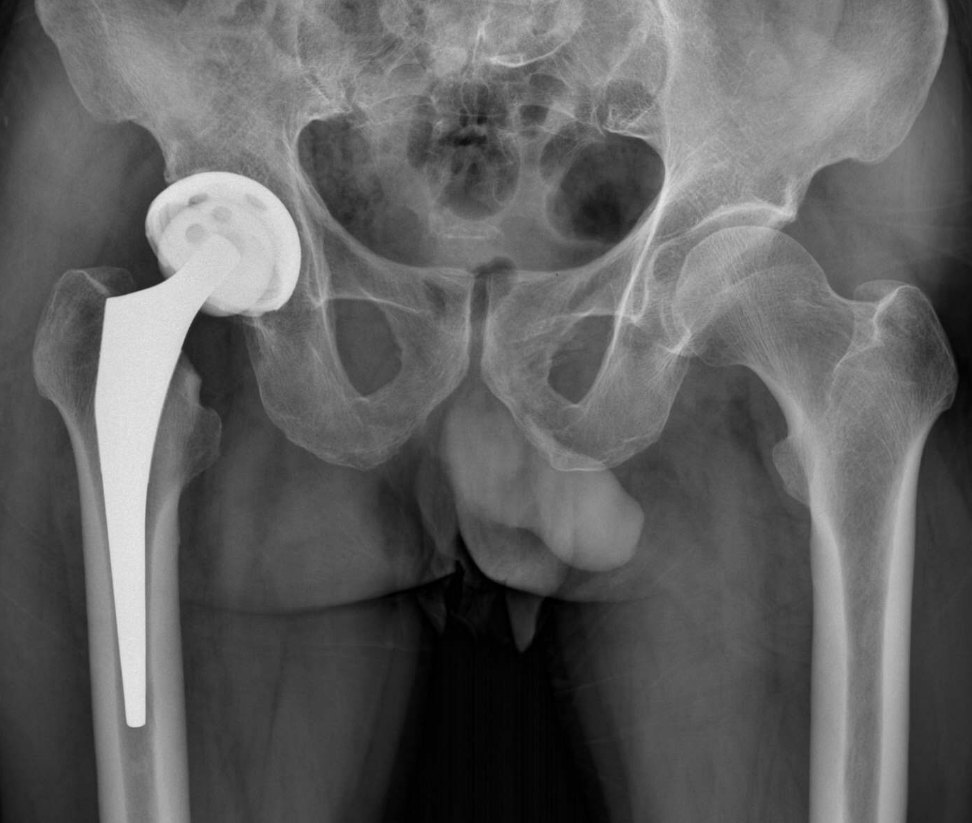

2、手術治療:對于嚴重骨頭壞死,可能需要進行手術治療,如骨移植、關節置換等,手術治療的效果因個體情況而異,需在專業醫生的指導下進行。